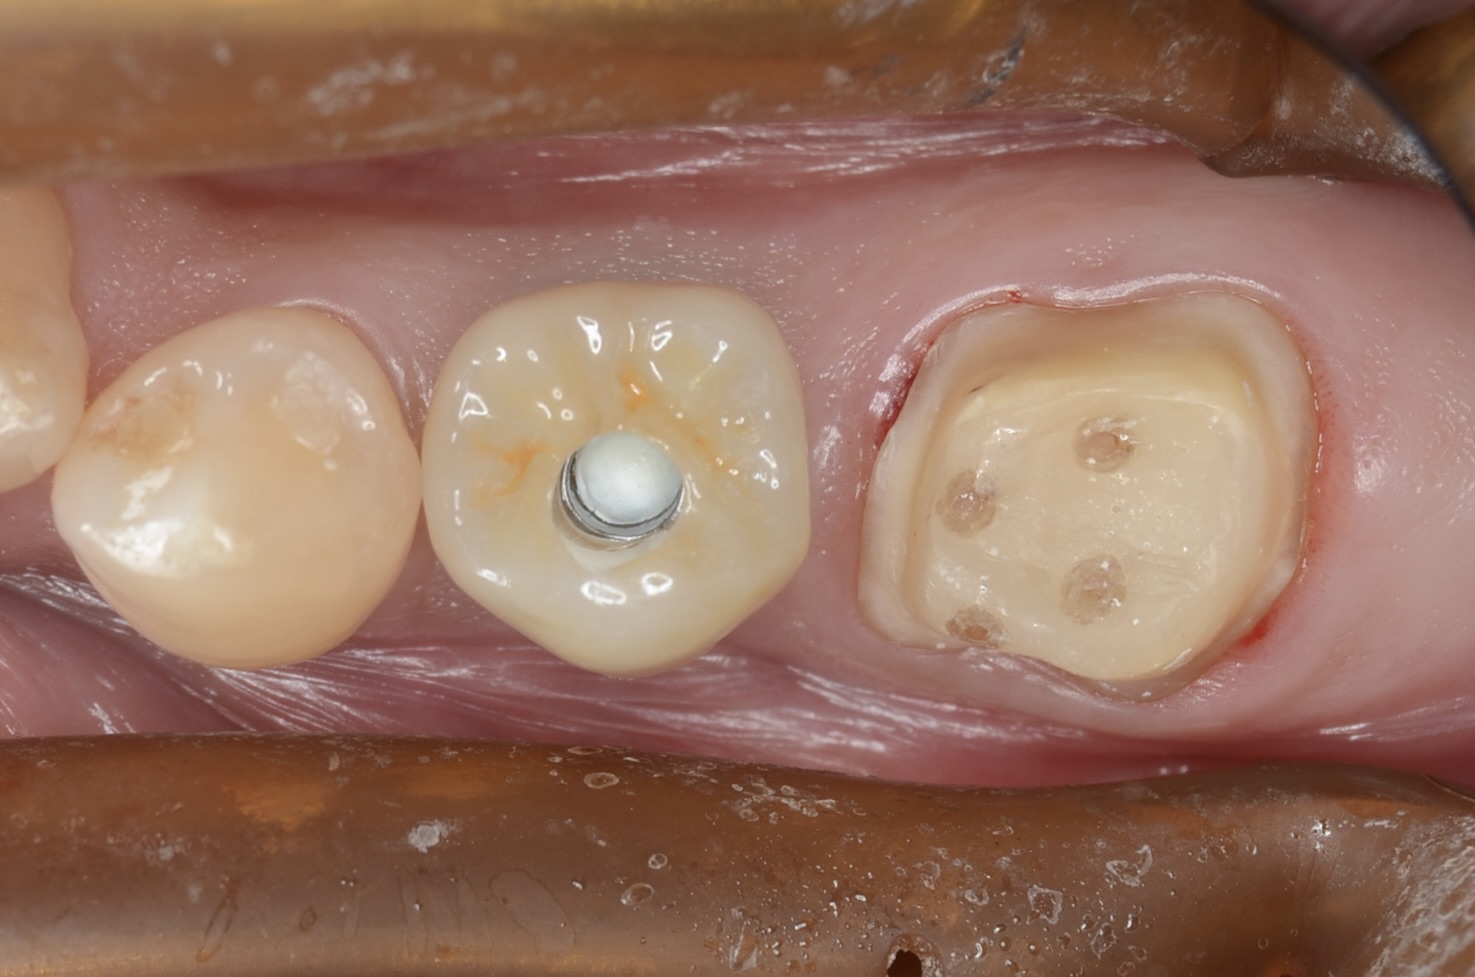

インプラント

まずインプラントからセットします。アクセスホールをレジンで埋めるので、ネジ穴にレジンが流れないように仮の蓋を入れておきます。 -

咬合面観

インプラントのアクセスホールをレジンで埋めて、7番にジルコニアクラウンが入りました。 -